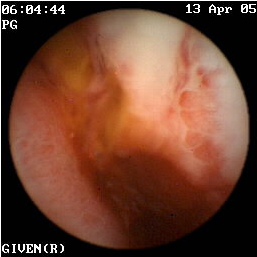

Η κάψουλα έχει επίσης ιδιαίτερη αξία στην ανεύρεση της εστίας της αιμορραγίας αγνώστου αιτιολογίας στη νόσο του Crohn (εικόνες 1,2). Οι Legnaniκαι συν του16 εκτίμησαν 11 ασθενείς με νόσο Crohnκαι αδιευκρίνιστη αιμορραγία και προσδιόρισαν την ακριβή αιτία της στους 9 από αυτούς.

1  2

Eικόνα 1. Βαριά φλεγμονή του βλεννογόνου             Εικόνα 2. Αυτόματη αιμορραγία ειλεού σε ασθενή

με σχηματισμό ψευδοπολύποδα.                             με γνωστή νόσο Crohn